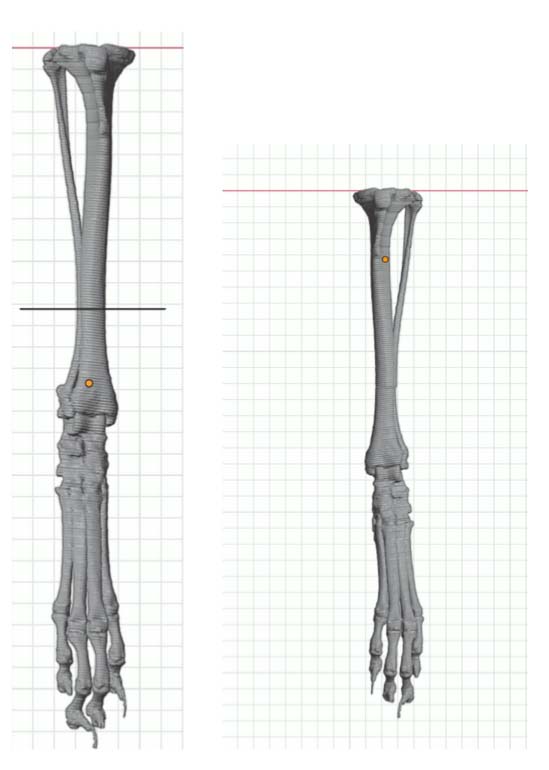

One right tibial deformity (19 degrees of excessive tibial internal torsion)

Correct the right femur angular limb deformities with a mid-diaphyseal oblique closing-wedge ostectomy centered at the CORA of the femoral deformity, which is located within the mid-diaphyseal (do not recommend a traditional distal femoral ostectomy (DFO) as this would result in a significant lateral femoral translation in this specific case). The trochlea is arthritic and hypoplastic, but not overtly deformed. In this case, a traditional block or wedge trochleoplasty is recommended rather than a patellar groove replacement (PGR). In addition, a corrective de-torsional tibial osteotomy has been recommended, as a tibial tuberosity transposition (TTT) is unlikely able to compensate for a torsion of this magnitude.

CT CAD-based surgical plan.

Right tibia distal diaphysis de-torsional osteotomy and internal fixation (medial contoured locking straight plate and screws (Ti))